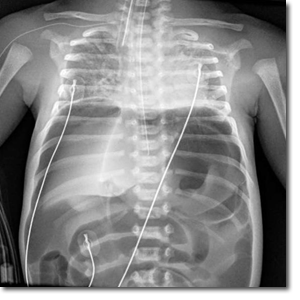

I­nes­ta­bi­li­dad y dis­ten­sión ab­do­mi­nal sú­bi­ta en un pre­ma­tu­ro de 32 se­ma­nas

Varón de 32 semanas de gestación, segundo gemelar, de 1850 g, nacido mediante cesárea urgente por amniorrexis prolongada, muerte del primer gemelo, leucocitosis y fiebre materna. Apgar 6/8. Precisa CPAP nasal las primeras horas de vida con buena evolución.